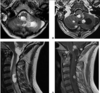

Which MR sequence can be used to detect acute cord hemorrhage?

T2* (susceptibility weighted images)

Dx: arachnoiditis: empty thecal sac sign.

Dx? 39yo male recently recovered from an URTI, presents w/bilateral lower extremity weakness & difficulty breathing.

Guillain-Barre syndrome: smooth, diffuse nerve root thickening & enhancement.